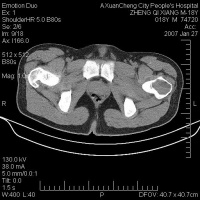

线所见 相当典型,尤其当肿瘤位于骨骺部位时。软骨母细胞瘤的溶骨区开始位于骨骺,倾向于越过生长软骨,向干骺端蔓延。在身体生长停止或即将停止时,生长软骨已经消失或即将消失时,如连续摄X线片,可清楚地看到肿瘤破坏和越过仍存在的生长软骨。

软骨母细胞瘤是一小或中度大小的肿瘤,直径从1~2cm到6~7cm。骨骺的溶骨常为中心性或偏心性。当肿瘤起源于肱骨大结节时,溶骨常位于肱骨近端,偏心性,圆形或轻度多环。其X线可透性不很强,可见云翳状或稀薄的弱的不透X线颗粒。

软骨母细胞瘤的界限明确,有时标骨硬化细线,很有特征性。在偏心性和较膨胀的病例中,皮质骨可膨胀至几乎消失。软骨母细胞瘤可侵蚀全部的软骨下骨,在干骺端皮质的部位,很少或没有骨膜反应